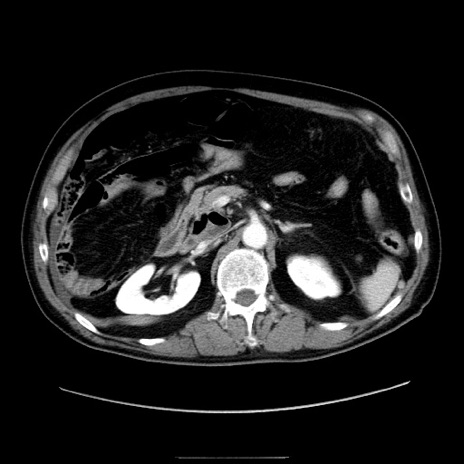

症例30(横断像)

【症例】80歳代男性

【主訴】臍周囲痛

【現病歴】約6時間前から臍下部痛が出現。次第に腹部膨隆・背部痛も生じてきたため来院。背部痛の場所は変化しない。

【身体所見】意識清明、BT 36.3℃、BP  131/87mmHg、P 87bpm、SpO2 100%(RA)、臍周囲自発痛・圧痛あり、反跳痛なし、自発痛部位に一致して板状硬あり、腹部膨隆、腸雑音減弱、CVA tenderness両側陰性。

【データ】WBC 19600、CRP 0.33